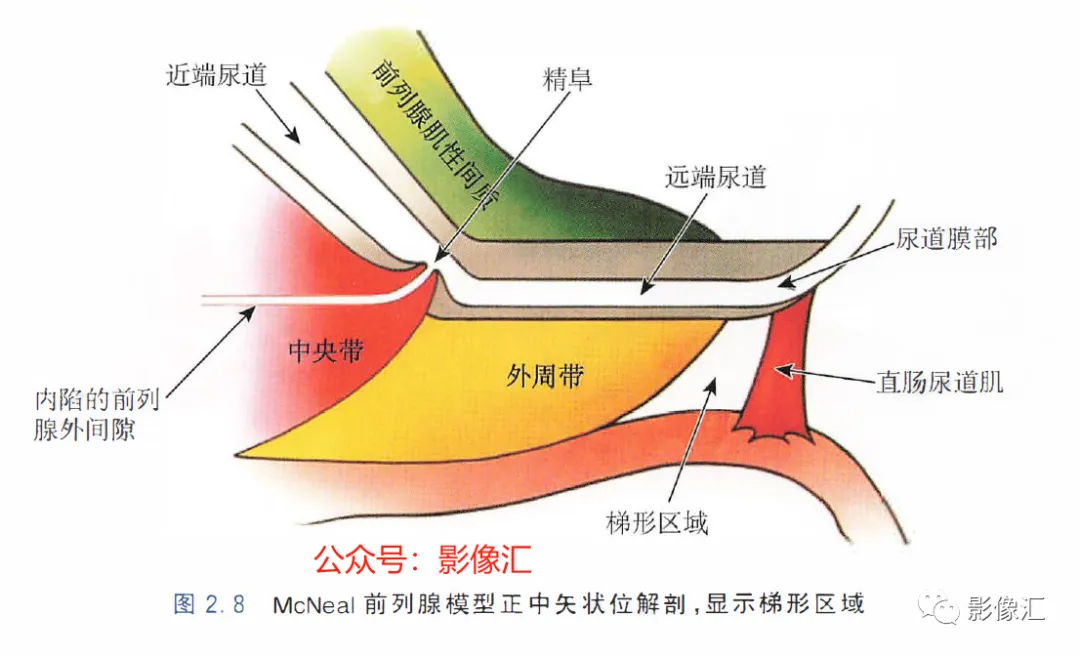

McNeal解剖模型认为前列腺根据周围不同结构环绕的关系而分为四个区域。尿道是描述整个前列腺区域解剖结构的解剖学标志。尿道由近端和远端尿道两个部分组成,每个部分约15mm长,由精阜分界。在精阜处,近端和远端尿道的走行呈35°。尿道壁由纵向走行的平滑肌纤维组成。围绕该内层的纵向肌肉层,是一层环形走行的肌层。两层平滑肌构成所谓的尿道内括约肌(IUS),其从膀胱颈延伸到尿道膜部的末端。IUS在膀胱颈的近端水平处最厚,随其向尿道膜部延伸,厚度逐渐减小。尿道膜部完整地被IUS环绕。在其前侧,前列腺内的lUS与前列腺肌性间质(AFMS)融合。两射精管走行方向与远端尿道平面平行,其开口于尿道腔内的前列腺小囊。移行带在前列腺组织中约占5%,构成两叶分别位于近端尿道两侧。其导管系统平行于尿道平面走行,止于精阜,射精管开口的近侧。移行带毗邻外周带,中央带和前列腺肌性间质,构成所谓的外科手术包膜,也就是说,确定了前列腺剜除术的外科手术平面。移行带和尿道周围腺体组织是良性前列腺增生(BPH)的发生部位。前列腺癌发生在移行带的比例为10%~20%。中央带在前列腺腺体组织中约占25%。其在前列腺底部形成金字塔形或锥形结构,在精阜水平处变窄至顶点。中央带的导管在射精管开口的两侧呈放射状走行。精囊和输精管穿入中央带形成射精管形似“精囊喙”。此区域由于缺乏前列腺包膜而成为解剖薄弱区。与射精管延续的中央带及伴行的筋膜和淋巴血管组织称为前列腺嵌入部(invaginated extraprostatic space,IES)。这是另一个解剖学上的薄弱区域,因此中央带疾病容易沿此区域播散。中央带相对发病率较低,发生在中央带的前列腺癌占5%~10%。外周带和中央带之间缺乏解剖学屏障,同时由于IES的存在,意味着前列腺尖部发生的肿瘤很容易进展到前列腺底部,并可早期造成前列腺周围间隙结构的受累。外周带约占前列腺腺体组织的70%。其包括前列腺表面的外侧、背侧和尖部,以多变的方式向腹侧延伸,与前纤维肌性间质相延续。前列腺不具有通常意义上的包膜结构,表面有一层腺样间质被称为“包膜"。前列腺“包膜”本身由纤维肌性间质构成,其在腺体周围形成一薄层结构。前列腺尖部没有这种间质层,造成一个解剖学上的蒲弱区域,称为梯形区域(trapezoidal area)。该区域腹侧以尿道膜部为界,背侧则以Denonvilliers和直肠筋膜为界,头侧以前列腺尖部(外周带)为界,尾侧则以直肠尿道肌为界。70%的前列腺癌发生在前列腺外周带。当前列腺癌起自前列腺尖部时,在早期即可通过梯形区域侵犯前列腺周围间隙。前列腺的背外侧神经血管蒂也是肿瘤易向外蔓延和侵袭的区域。AFMS约占前列腺体积的33%,是前列腺的非腺体区域,构成前列腺的前表面。在其最近端部分,其与逼尿肌和尿道内括约肌(IUS)的平滑肌纤维融合。头侧,其保持和尿道外括约肌(EUS)的关系;EUS的横纹肌纤维在该区域(前列腺尖部的前外侧)融合,构成前列腺外括约肌群。有四个“解剖薄弱“ 区域,通过这些区域,前列腺肿瘤可以生长并侵犯相邻的结构。这些区域是:精囊喙(图2. 6和图2. 17)

前列腺尖部是用于表示前列腺腺体尾侧(最下方)的术语,与尿道膜部密切接触。前列腺尖部可显示出不同的形态:圆环形或腹侧,背侧或两侧突出(图2. 9和图2.10) ,了解前列腺尖部形态的重要性主要在于两点:(1)前列腺尖部或多或少与EUS(尿道膜部的横纹肌纤维)头侧区域重叠(或覆盖),这些纤维部分融入前列腺尖部(图2.11)。在接受根治性前列腺切除术的患者中,有必要采用能够外翻(exteriorising)和解剖这部分横纹肌纤维的手术技术, 以保持控尿功能(图2.12)。(2)在根治性前列腺切除术中必须避免阳性边缘 。值得注意的是,在尖部水平,腺体组织仅为外周带组织,尖部仅前缘一小部分为AFMS。此外,前列腺尖部构成所谓的梯形区域的顶部,这是众所周知的解剖薄弱区域,在该区域前列腺癌可更易侵犯至前列腺间隙(图2.8)。在其前外侧,前列腺尖部由外括约肌群覆盖,与AFMS及从膀胱颈延伸来的由平滑肌构成的逼尿肌群相融合(图2. 13)。前列腺尖部尾侧与尿道膜部起始部相延续。男性的尿道膜部被认为是位于前列腺尖部和尿道球部之间的尿道部分,长度约为1cm。其内有尿道内括约肌(IUS)和尿道外括约肌(EUS)。IUS从膀胱颈(此处最厚)延伸到尿道球部,沿尾侧方向厚度逐渐减小。IUS环尿道膜部,由双层平滑肌纤维组成,包括内层纵行肌和外部的环形肌(图2. 13和图2. 14)。IUS的神经支配来自自主神经、交感神经和副交感神经系统。下腹下神经丛负责前列腺、前列腺尖部和尿道膜部的所有自主神经支配。其终末支沿内侧走行达耻骨上肌,外侧走行达尿道膜部的EUS,在腹侧构成所谓的阴茎海绵体神经(负责勃起机制)和尿道海绵体神经(负责尿道膜部黏膜的自主神经传入,直接与控尿机制有关(图2 . 13 和图2. 14)。EUS构成横纹肌平面(横纹肌纤维),在尿道膜部水平围绕IUS,在前列腺尖部的前外侧上扩展,并在该水平上构成所谓的EUS围裙(图2. 13)。其肌纤维主要是I 型(即没有肌梭),尽管强度低,但专门负责长时间收缩。EUS的功能在于排尿间期保持尿道腔塌陷,从而防止无意识的尿液渗漏。EUS最厚处位于尿道膜部水平,厚度向头侧逐渐减小,最终构成前列腺围裙。该围裙以Ω(希腊字母“欧米伽”)形围绕尿道膜部,而后正中不包绕, 形成“后正中脊”(图2. 13 和图2. 14)。此外,EUS的部分横纹肌纤维融入到前列腺尖部的下部,位于精阜下方,融入纤维的多少依赖于前列腺尖部形态(图2. 11) 。EUS的神经支配和动脉供血分别来自外阴神经和外阴内动脉。该神经为躯体神经,因此EUS可随意控制。外阴内神经和动脉均向头侧走行,至会阴深横肌处,发出分支支配EUS最尾侧部分,随后形成阴茎背侧神经脊背侧动脉。前列腺尖部与支配EUS的外阴内动脉的分支之间距离为3~13mm (图2. 13)。IUS和EUS构成所谓的控尿被动及内在因素。它们的功能基本上是“塌陷”尿道至“后正中脊”,这样可防止排尿间期无意识的尿液“泄露”(图2.11和2.13)。阴茎海绵体神经在前列腺周围筋膜的后外侧及前外侧走行。手术操作时保留这些外侧神经对于确保前列腺根治术后勃起功能的恢复是至关重要的。会阴体是一纤维肌性结构,难以在解剖上进行评估,其功能是支持所有构成会阴部及支撑盆腔脏器的肌肉及腱膜结构。对于控尿,会阴体形成一固定的底盘,通过将EUS的横纹肌平面压至底盘处,从而可使EUS正确发挥功能,这样在排尿间期可以正确地使尿道塌陷。会阴体由以下结构组成(图2.13)和图2.14)。

- 识别解剖薄弱区域:①精囊喙;②前列腺嵌入部(IES);③前列腺蒂周围间隙;④梯形区域。

- 由于以下几点,前列腺尖部是腺体的重要组成部分:①其腺体组织与McNeal外周带结合;②与梯形区域毗邻;③不同程度的覆盖外括约肌(EUS)。